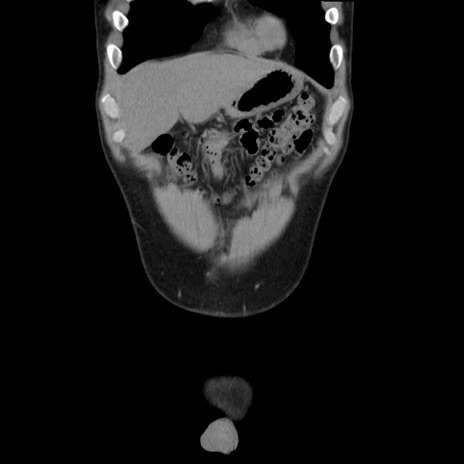

症例36(冠状断像)

【症例】20歳代 男性

【主訴】心窩部痛

【現病歴】今朝より上腹部痛あり。一旦軽快していたが再度出現したため救急要請。昨日夕に白身の魚を含む刺身を食べた。

【身体所見】BP 136/89mmHg、HR 74/min、BT 37.0℃、腹部:膨満、軟、心窩部に圧痛あり。反跳痛なし、筋性防御なし、腸雑音やや亢進あり。

【データ】WBC 17700、CRP 0.48